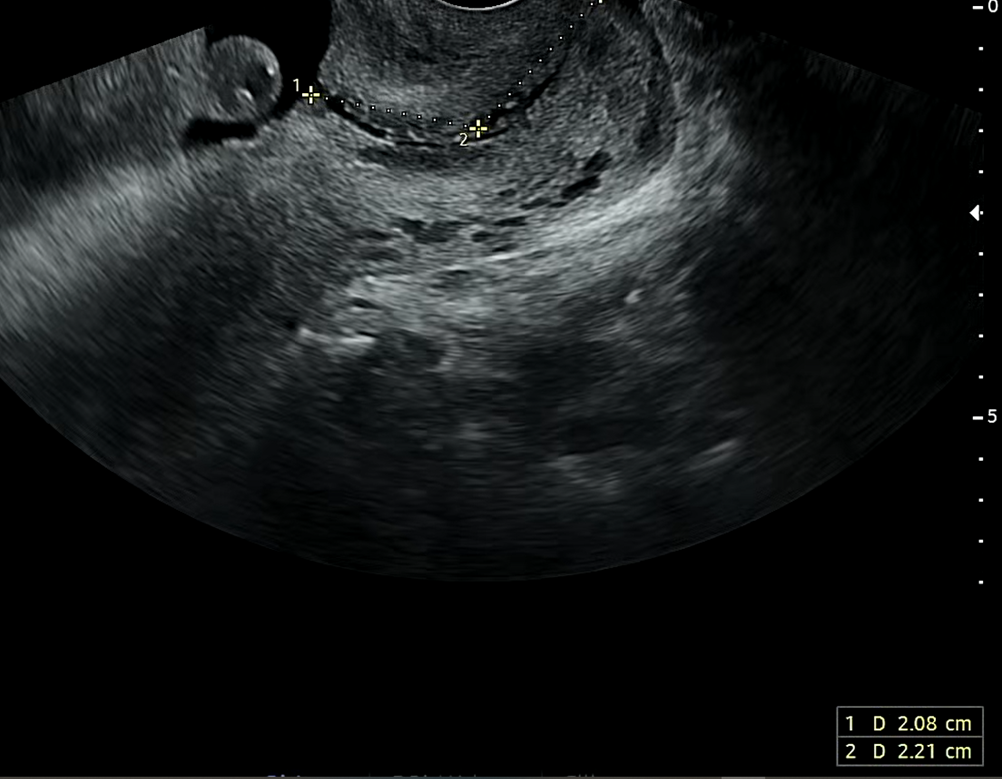

호띵엄마 자궁경부길이

총 4.29cm로 자궁경부길이는 양호하다고 한다. 1시간 가량 산책해도 문제없다고 하셨다는데 앞으로 시간날때 호띵엄마랑 더 자주 산책을 나갈 예정이다. 우리 호띵이가 잘크고 있어 기분이 좋았다.